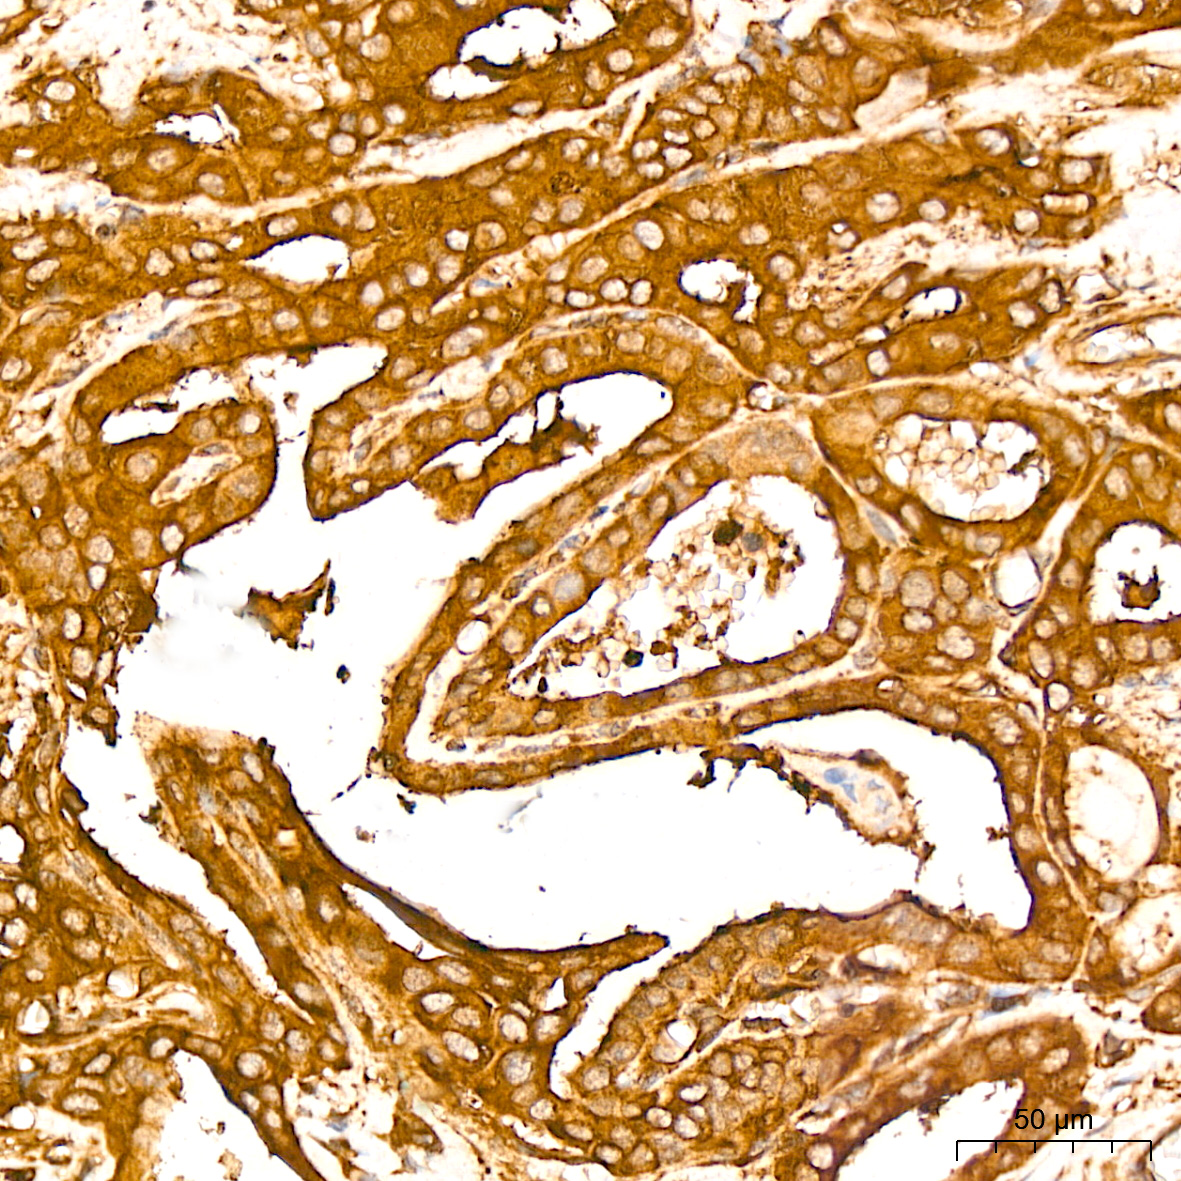

| Immunohistochemistry analysis of paraffin-embedded Human thyroid cancer tissue using NF-kB p65/RelA Rabbit mAb (A19653) at a dilution of 1:800 (40x lens). High pressure antigen retrieval performed with 0.01M Citrate Bufferr (pH 6.0) prior to IHC staining. |